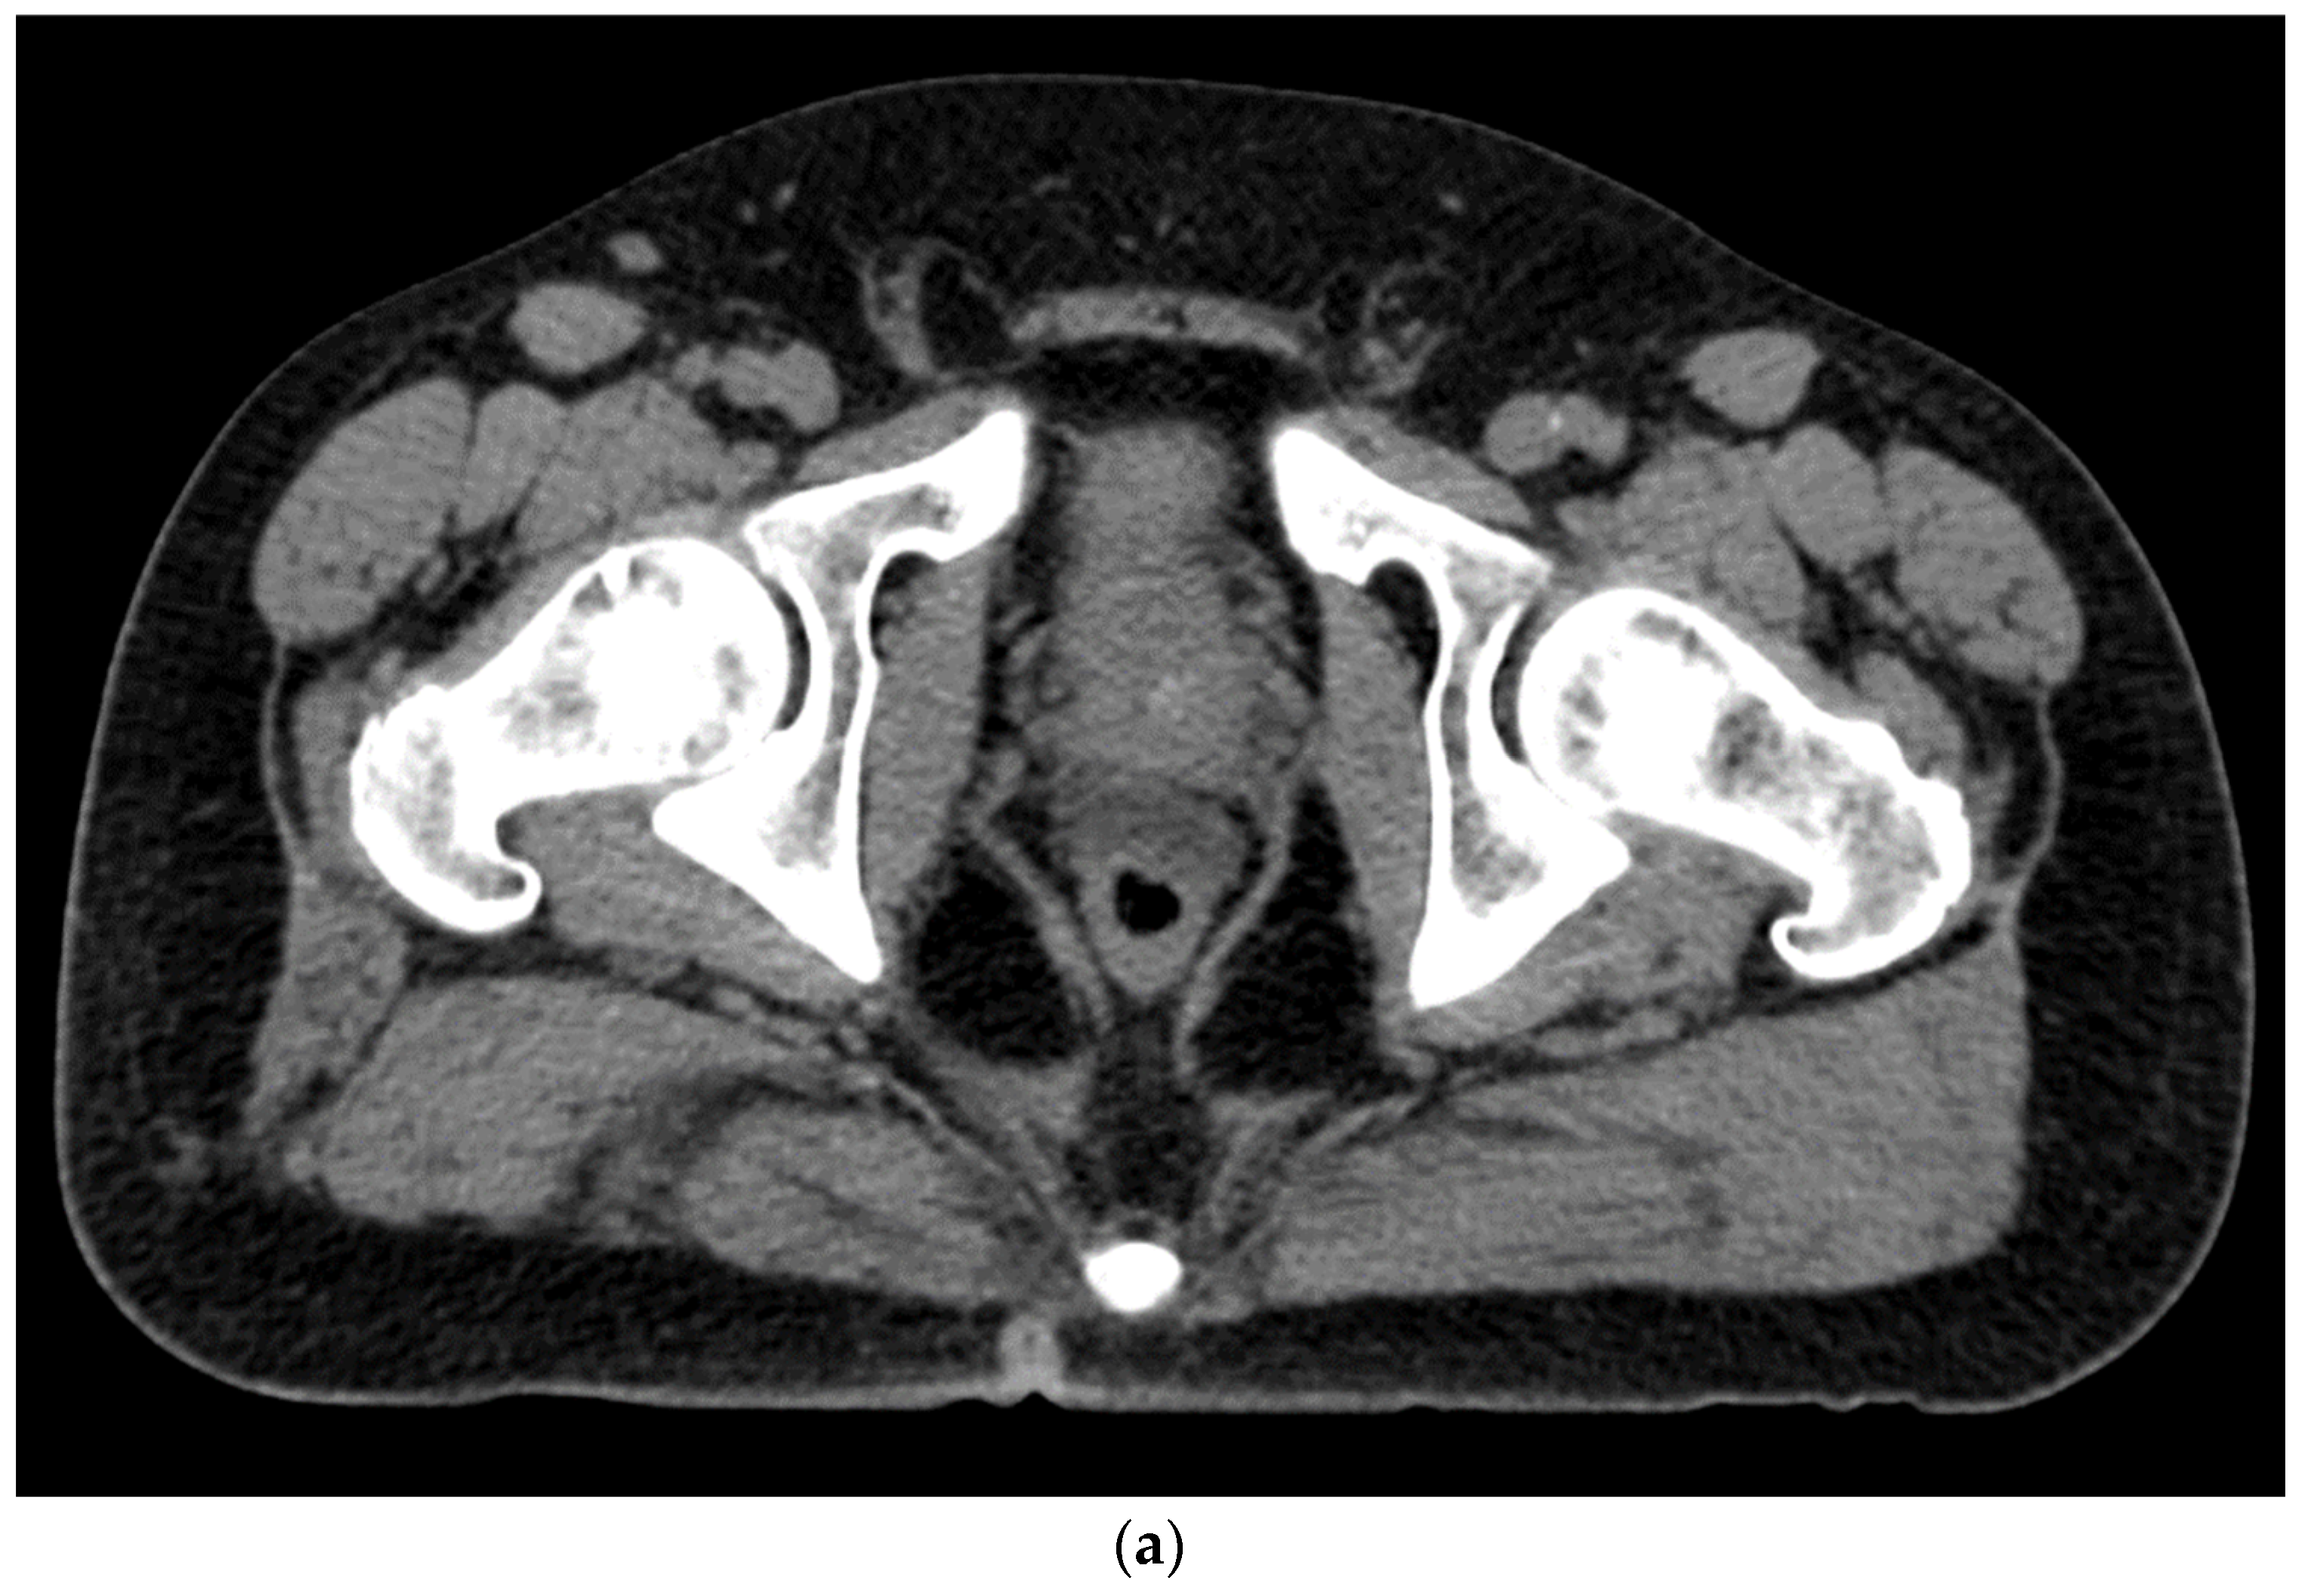

6. Placement

- Kamran, S.C.; McClatchy, D.M., 3rd; Pursley, J.; Trofimov, A.V.; Remillard, K.; Saraf, A.; Ghosh, A.; Thabet, A.; Sutphin, P.; Miyamoto, D.T.; et al. Characterization of an Iodinated Rectal Spacer for Prostate Photon and Proton Radiation Therapy. Pract. Radiat. Oncol. 2022, 12, 135–144. [Google Scholar] [CrossRef]

- SpaceOAR™ Vue System. 2022. Available online: https://www.bostonscientific.com/content/dam/bostonscientific/spaceoar/vue/URO-855204-AA%20SpaceOAR%20VUE_Brief%20Summary.pdf (accessed on 9 August 2022).

- SpaceOAR Vue™ Hydrogel. 2020. Available online: https://www.bostonscientific.com/content/dam/bostonscientific/spaceoar/vue/SpaceOAR-Vue-Hydrogel-Brochure.pdf (accessed on 9 August 2022).

- Brenneman, R.J.; Andruska, N.; Roy, A.; Waters, M.R.; Fischer-Valuck, B.W.; Schiff, J.P.; Goddu, S.M.; Henke, L.E.; Gay, H.A.; Baumann, B.C.; et al. Characterization of a Novel Radiopaque Perirectal Hydrogel Spacer for Prostate Cancer Radiotherapy. Int. J. Radiat. Oncol. Biol. Phys. 2021, 111, e536. [Google Scholar] [CrossRef]

- Conroy, D.; Becht, K.; Forsthoefel, M.; Pepin, A.N.; Lei, S.; Rashid, A.; Collins, B.T.; Lischalk, J.W.; Suy, S.; Aghdam, N.; et al. Utilization of Iodinated SpaceOAR Vue During Robotic Prostate Stereotactic Body Radiation Therapy (SBRT) to Identify the Rectal-Prostate Interface and Spare the Rectum: A Case Report. Front. Oncol. 2020, 10, 607698. [Google Scholar] [CrossRef]

- Gross, A.; Yuan, J.; Spratt, D.; Fredman, E. Case Report: Role of an Iodinated Rectal Hydrogel Spacer, SpaceOAR Vue, in the Context of Low-Dose-Rate Prostate Brachytherapy, for Enhanced Post-Operative Contouring to Aid in Accurate Implant Evaluation and Dosimetry. Front. Oncol. 2021, 11, 810955. [Google Scholar] [CrossRef]